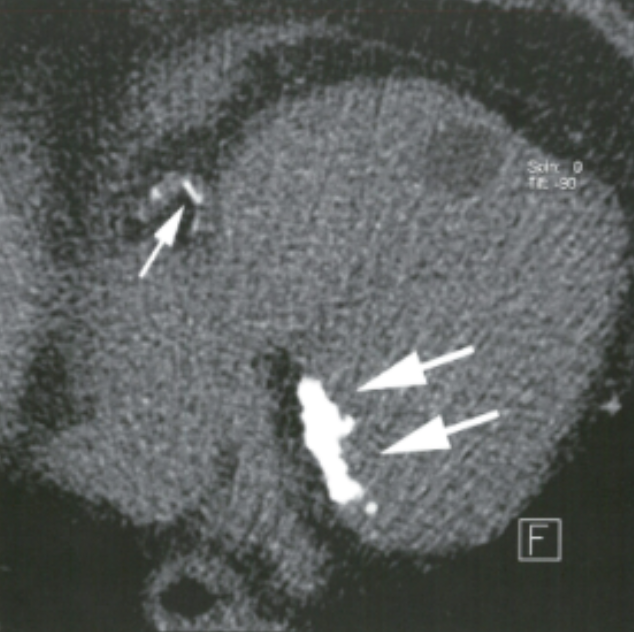

Describe the findings:

Coronary Sinus

Describe the findings and most likely finding on coronary angiorgram

Occlusion in LCFx territory